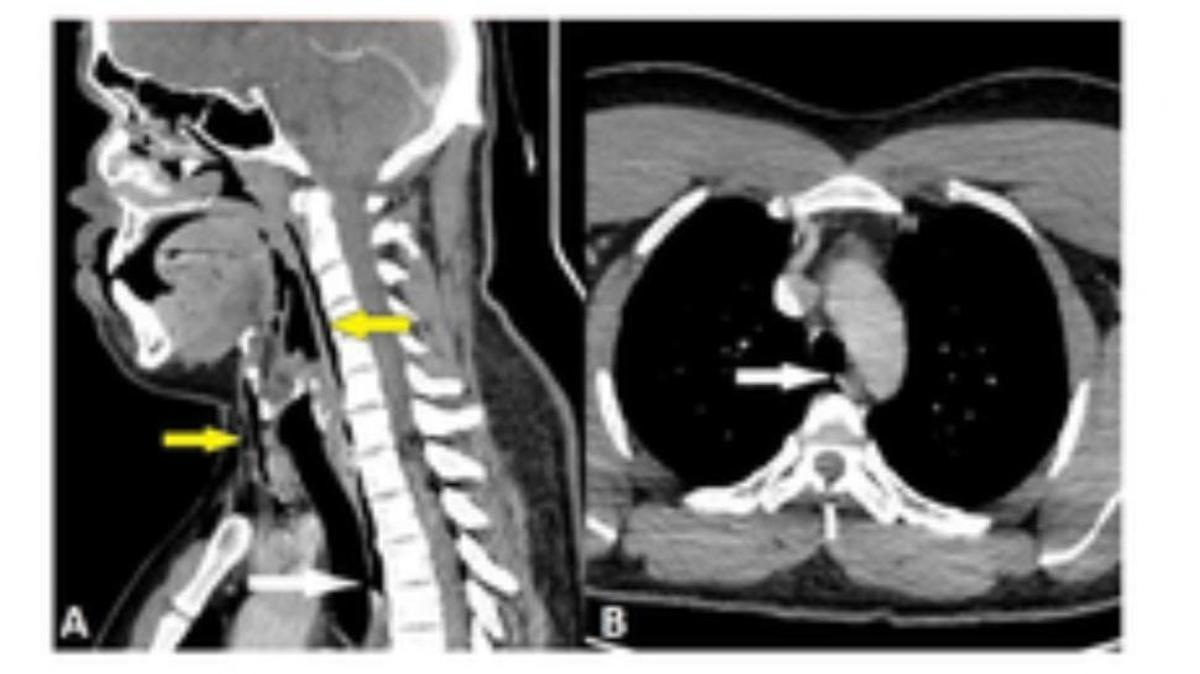

Bersama hasil CT scan Menunjukkan adanya robekan yang terbentuk Ke Di tulang ketiga dan keempat Ke leher pasien. Situasi itu memungkinkan udara keluar Bersama tenggorokannya atau trakea, dan masuk Hingga jaringan leher serta ruang Ke Di paru-paru.

Diketahui bahwa lubang Ke trakeanya berukuran 0,08 x 0,08 inci atau Disekitar 2×2 milimeter (mm).